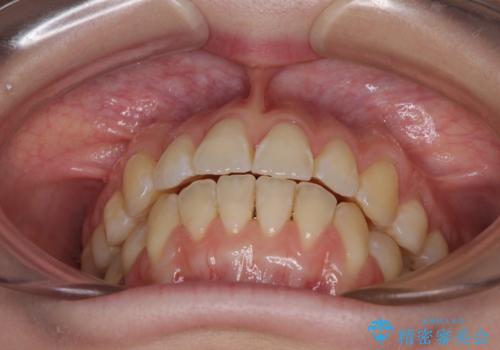

気になるデコボコとオープンバイト インビザラインでの矯正治療

- 前歯のデコボコと上下が開いていることを気にして来院された患者様です。

いわゆるオープンバイトは、インビザラインによる治療が適しているため、インビザラインにて治療を行うこととしました。

オープンバイトは容易に後戻りを起こすため、少しでも後戻りリスクを軽減するために舌癖改善のトレーニングをしっかりと行っていただきました。